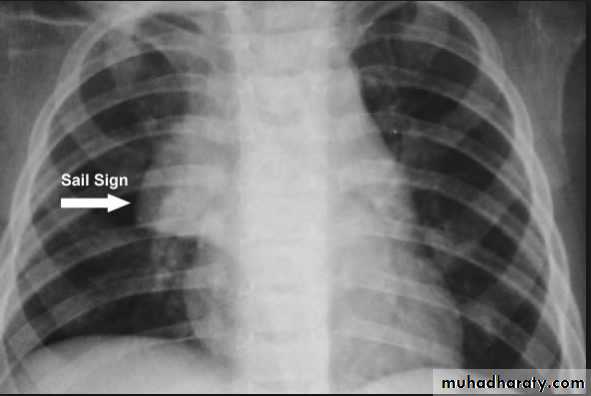

Atelectasis